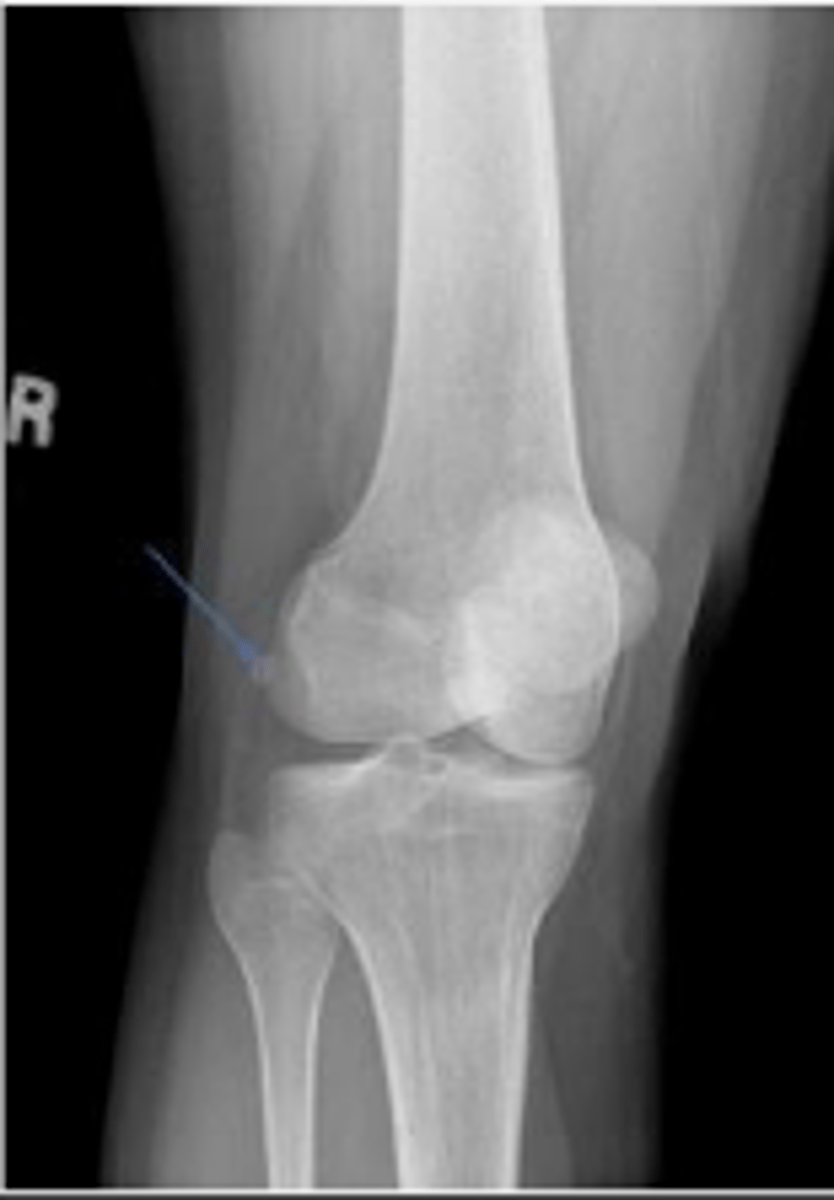

Right AP knee

What is the name of the radiographic view?